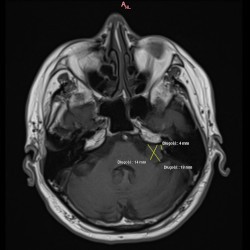

Guz lewego kąta mostowo-móżdżkowego

W dn. 15.09.2021 do Poradni Radioterapii zgłosił się chory z niedosłuchem lewostronnym i zaburzeniami równowagi. W wyniku MRI głowy w lewym kącie mostowo-móżdżkowym widoczna była lita masa silnie wzmacniającego się guza, który cienką wypustką wpuklał się do światła przewodu słuchowego wew.